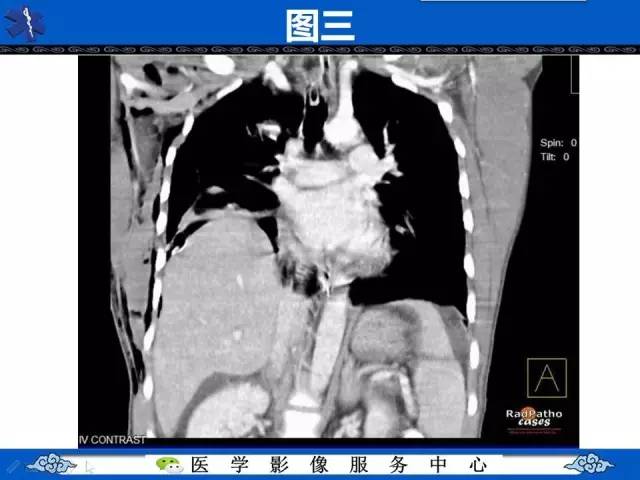

圆锥面包征——膈肌破裂

【影像征象】圆锥面包征——膈肌破裂